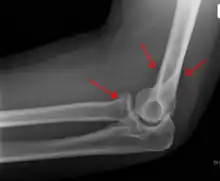

Fracture du radius proximal

La fracture peut se produire dans la capsule de l'articulation du coude. Elle n'est pas nécessairement visible directement sur une radio mais peut être détectée par le déplacement des coussinet adipeux suite à l'épanchement articulaire par le "signe du voile".

La lésion d'Essex-Lopresti est une fracture de la tête du radius concomitante avec une luxation de l'articulation radio-ulnaire distale et une lésion de la membrane interosseuse de l'avant-bras[2].